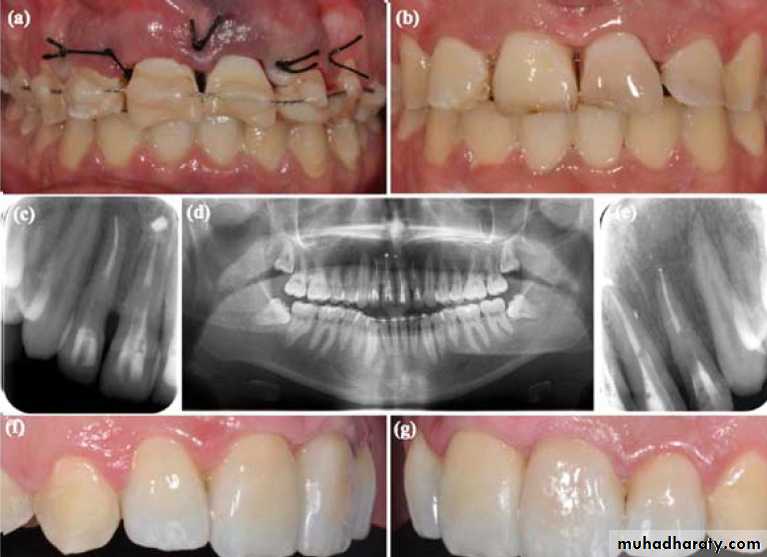

Gentle reinsertion of the tooth into the socket followStabilization

To immobilize the tooth with a semi- rigid splint for (7 -10) daysThe splint should not interfere with the patient’s capability to perform correct hygiene

It should allow a physiological movement of the tooth.

In cases of bone fracture, the tooth should be splinted for a longer period, (1 or 2 months), depending on the clinical situation. Rigid immobilization is constrain- dictated, except incases of root fracture

After the immobilization, a radiograph should be taken to verify the correct position of the tooth/teeth.

Stabilization

Types of splinting

• Acid-etched composite splinting

• Interdental wiring

• (Vacuum- formed plastic ) splint

• Arch bare splint

More rigid and the longer the stabilization, the more root resorption, amyloses that can be expected

Acid-etched composite splinting